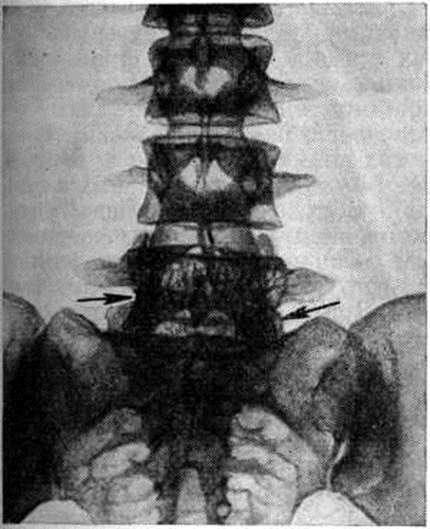

Для распознавания Гемангиома применяют рентгенографию (смотри), томографию (смотри), а в сложных случаях — ангиографию (смотри). При рентгенологическое исследовании обнаруживаются костные Гемангиома, гемангиомы мягких тканей (при наличии ангиолитов) и смешанные — преимущественно в телах нижних грудных и поясничных позвонков, а также в плоских костях черепа. Рентгенологическое картина поражённого по звонка (рисунок 1) характеризуется повышением прозрачности тела позвонка, образованием грубых, вертикально направленных трабекул или мелкоячеистой структурой в виде отдельных округлых просветлений, разделённых довольно плотными перегородками. Кроме того, наблюдается деформация позвонка в виде «вздутия» тела позвонка, когда его «талия» сглаживается и даже выбухает кпереди и в стороны. Частым осложнением Гемангиома является компрессионный перелом с уменьшением высоты тела позвонка и вдавлением межпозвоночного диска (верх него чаще, чем нижнего). Поражение межпозвоночных дисков, как правило, отсутствует, что служит важным дифференциально-диагностическим признаком Гемангиома, позволяющим исключить воспалительный характер процесса.

Рис. 1. | ||